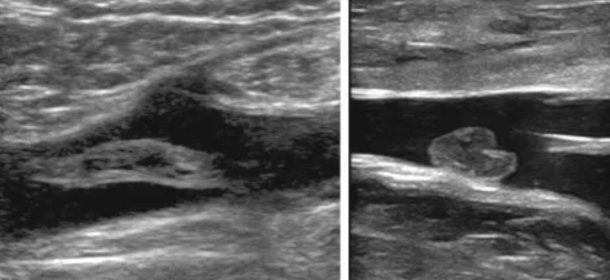

Normal

2 exemples de caillots de TVP

Syndrome post-thrombotique

- Insuffisance veineuse chronique

- Suite à une TVP

- Du à une insuffisance valvulaire

- Clinique: Douleurs, gonflements, varices, décolorationThrombose veineuse profonde MI membres inférieurs superficielle